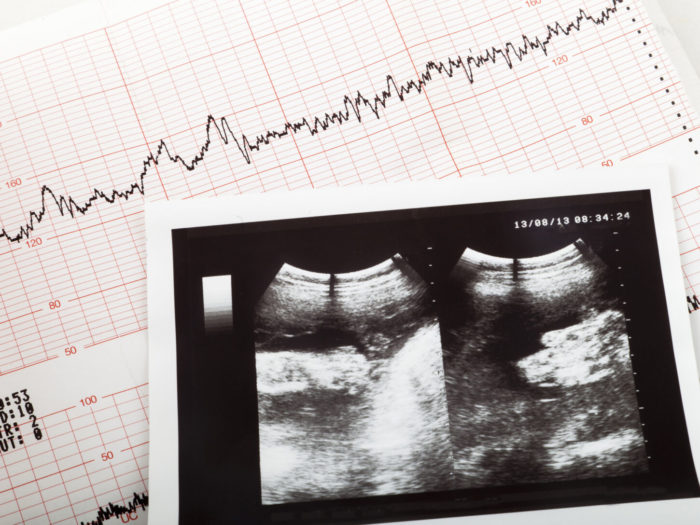

El proyecto de ley conocida como «Ley del latido», busca que sea obligatorio realizar un ultrasonido a toda mujer que solicite un aborto.

El ultrasonido debe ser “realizado por personal capacitado e idóneo de conformidad con las prácticas médicas estándares, a los efectos de determinar la detección de latidos fetales”.

Si este estudio detecta latidos fetales del bebé no nacido entonces este no podrá ser eliminado.

El proyecto explica que “los médicos, personal de salud y/o sistemas de salud no podrán realizar o inducir intencionalmente un aborto o interrupción del embarazo, si se detecta un latido cardíaco del/de los feto/s o niño/s en gestación, entendido el mismo como actividad cardíaca o contracción rítmica constante y repetitiva del corazón fetal, dentro del saco gestacional”.

El primer latido de un bebé se produce a los 16 días de la concepción.

Sin embargo, en general es a partir de las 6 ½ -7 semanas en que un latido del corazón puede ser detectado con la tecnología que existe en cualquier centro de salud.

Tras detectarse el latido ello implica un eficaz obstáculo para emprender el descarte de un ser humano en gestación.